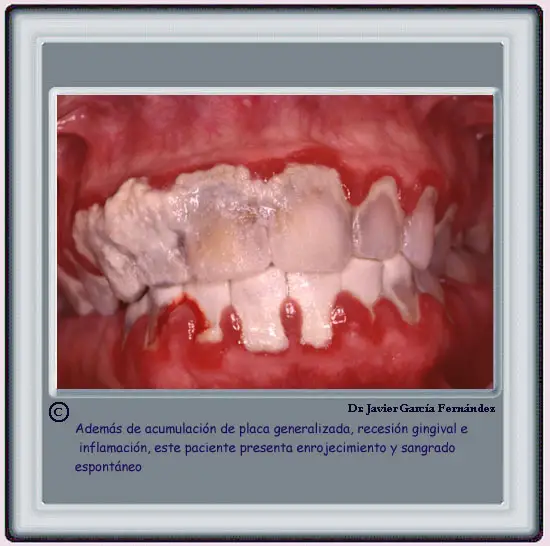

Página anterior Acumulación generalizada de placa Página siguiente